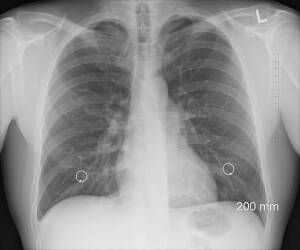

Die Krankheit Sarkoidose mag zwar oft im medizinischen Schatten stehen, doch für die Betroffenen stellt sie eine erhebliche Herausforderung dar. Diese chronische, entzündliche Erkrankung tritt häufig in der Lunge auf, kann jedoch andere Organe angreifen und führt oft zu Symptomen, die das Alltagsleben erheblich beeinträchtigen. Herzrhythmusstörungen, Lungenfibrose oder sogar neurologische Ausfälle können zu den vielschichtigen Komplikationen zählen. Traditionell greift die Schulmedizin bei solchen Krankheitsbildern auf entzündungshemmende Medikamente zurück, allen voran Kortison. Die Frage bleibt jedoch, ob es über Kortison hinaus Optionen gibt, die heilend und unterstützend wirken können, ohne dabei in den Hormonhaushalt einzugreifen oder langwierige Nebenwirkungen zu verursachen.